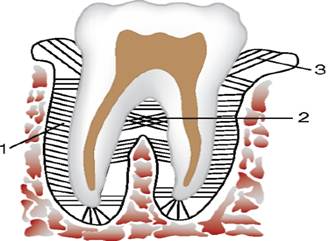

В стоматологии различают клиническую коронку (corona clinica), под которой понимают участок зуба, выступающий над десной, а также клинический корень (radix clinica) - участок зуба, находящийся в альвеоле. Клиническая коронка с возрастом вследствие атрофии десны увеличивается, а клинический корень уменьшается. Внутри зуба имеется небольшая полость зуба (cavitas dentis), форма которой разная в различных зубах. В коронке зуба форма ее полости (cavitas coronae) почти повторяет форму коронки. Далее она продолжается в корень в виде канала корня (canalis radicis dentis), который заканчивается на верхушке корня отверстием (foramen apices dentis). В зубах с 2 и 3 корнями имеется, соответственно, 2 или 3 корневых канала и верхушечных отверстия, но каналы могут ветвиться, раздваиваться и вновь соединяться в один. Стенка полости зуба, прилежащая к его поверхности смыкания, называется сводом. В малых и больших коренных зубах, на окколюзионной поверхности которых имеются жевательные бугорки, в своде заметны соответствующие углубления, заполненные рогами пульпы. Поверхность полости, от которой начинаются корневые каналы, называется дном полости. В однокорневых зубах дно полости воронкообразно суживается и переходит в канал. В многокорневых зубах дно более плоское и имеет отверстия для каждого корня. Полость зуба заполнена пульпой зуба (pulpa dentis) - рыхлой соединительной тканью особого строения, богатой клеточными элементами, сосудами и нервами. Соответственно частям полости зуба различают пульпу коронки (pulpa coronalis) и пульпу корня (pulpa radicularis). Общее строение зуба. Твердую основу зуба составляет дентин (dentinum) - вещество, сходное по строению с костью. Дентин определяет форму зуба. Образующий коронку дентин покрыт слоем белой зубной эмали (enamelum), а дентин корня - цементом (cementum). Место соединения эмали коронки и цемента корня приходится на шейку зуба. Возможны 3 вида соединения эмали с цементом: 1) они соединяются встык; 2) они перекрывают друг друга (эмаль перекрывает цемент и наоборот); 3) эмаль не доходит до края цемента и между ними остается открытый участок дентина. Эмаль неповрежденных зубов покрыта прочной, лишенной извести кутикулой эмали (cuticula enameli). Дентин является первичной тканью зубов. По структуре он сходен с грубоволокнистой костью и отличается от нее отсутствием клеток и большей твердостью. Дентин состоит из отростков клеток - одонтобластов, которые находятся в периферическом слое пульпы зуба, и окружающего их основного вещества. В нем имеется очень много дентинных трубочек (tubuli dentinales), в которых проходят отростки одонтобластов. В 1 мм3 дентина насчитывается до 75 000 дентинных трубочек. В дентине коронки вблизи пульпы трубочек больше, чем в корне. Число дентинных трубочек неодинаково в различных зубах: в резцах их в 1,5 раза больше, чем в молярах.

Строение зуба: 1 - эмаль; 2 - дентин; 3 - пульпа; 4 - свободная часть десны; 5 - периодонт; 6 - цемент; 7 - канал корня зуба; 8 - стенка альвеолы; 9 - отверстие верхушки зуба; 10 - корень зуба; 11 - шейка зуба; 12 - коронка зуба

Корень зуба прикрепляется к альвеоле челюсти посредством множества пучков соединительнотканных волокон. Эти пучки, рыхлая соединительная ткань и клеточные элементы образуют соединительнотканную оболочку зуба, которая находится между альвеолой и цементом и называется периодонтом (periodontium). Периодонт играет роль внутренней надкостницы. Такое прикрепление является одним из видов фиброзного соединения - зубоальвеолярным соединением (articulation dentoalveolaris). Совокупность окружающих зубной корень образований: периодонт, альвеола, соответствующий ей участок альвеолярного отростка и покрывающая его десна, называется пародонтом (pamdontium). Строение периодонта. Фиксация зуба осуществляется при помощи периодонта, волокна которого натянуты между цементом и костной альвеолой. Совокупность трех элементов (костная зубная альвеола, периодонт и цемент) называют поддерживающим аппаратом зуба. Периодонт представляет собой комплекс соединительнотканных пучков, расположенных между костной альвеолой и цементом. Ширина периодонтальной щели зубов человека составляет возле устья альвеолы 0,15- 0,35 мм, в средней трети корня 0,1- 0,3 мм, у верхушки корня 0,3-0,55 мм. В средней трети корня периодонтальная щель имеет перетяжку, поэтому условно ее можно сравнить по форме с песочными часами, что связано с микродвижениями зуба в альвеоле. После 55-60 лет периодонтальная щель суживается (в 72% случаев). Множество пучков коллагеновых волокон идет от стенки зубной альвеолы к цементу. В промежутках между пучками фиброзной ткани находятся прослойки рыхлой соединительной ткани, в которой лежат клеточные элементы (гистиоциты, фибробласты, остеобласты и др.), сосуды и нервы. Направление пучков коллагеновых волокон периодонта неодинаково в различных отделах. В устье зубной альвеолы (краевой периодонт) в удерживающем аппарате можно выделить зубодесневую, межзубную и зубоальвеолярную группы пучков волокон. Зубодесневые волокна (fibrae dentogingivales) начинаются от цемента корня у дна десневого кармана и распространяются веерообразно кнаружи в соединительную ткань десны. Пучки хорошо выражены на вестибулярной и оральной поверхностях и сравнительно слабо на контактных поверхностях зубов. Толщина пучков волокон не превышает 0,1 мм. Межзубные волокна (fibrae interdentaliae) образуют мощные пучки шириной 1,0-1,5 мм. Они простираются от цемента контактной поверхности одного зуба через межзубную перегородку к цементу соседнего зуба. Эта группа пучков выполняет особую роль: сохраняет непрерывность зубного ряда и участвует в распределении жевательного давления в пределах зубной дуги. Зубоальвеолярные волокна (fibrae dentoalveolares) начинаются от цемента корня на всем протяжении и идут к стенке зубной альвеолы. Пучки волокон начинаются на верхушке корня, распространяются почти вертикально, в приверхушечной части - горизонтально, в средней и верхней третях корня они идут косо снизу вверх. На многокорневых зубах пучки идут менее косо, в местах разделения корня следуют сверху вниз, от одного корня к другому, перекрещиваясь друг с другом. При отсутствии зуба-антагониста направление пучков становится горизонтальным. Ориентировка пучков коллагеновых волокон периодонта, а также структура губчатого вещества челюстей формируются под влиянием функциональной нагрузки. В зубах, лишенных антагонистов, со временем количество и толщина пучков периодонта становятся меньше, а их направление из косого превращается в горизонтальное и даже в косое в противоположном направлении.